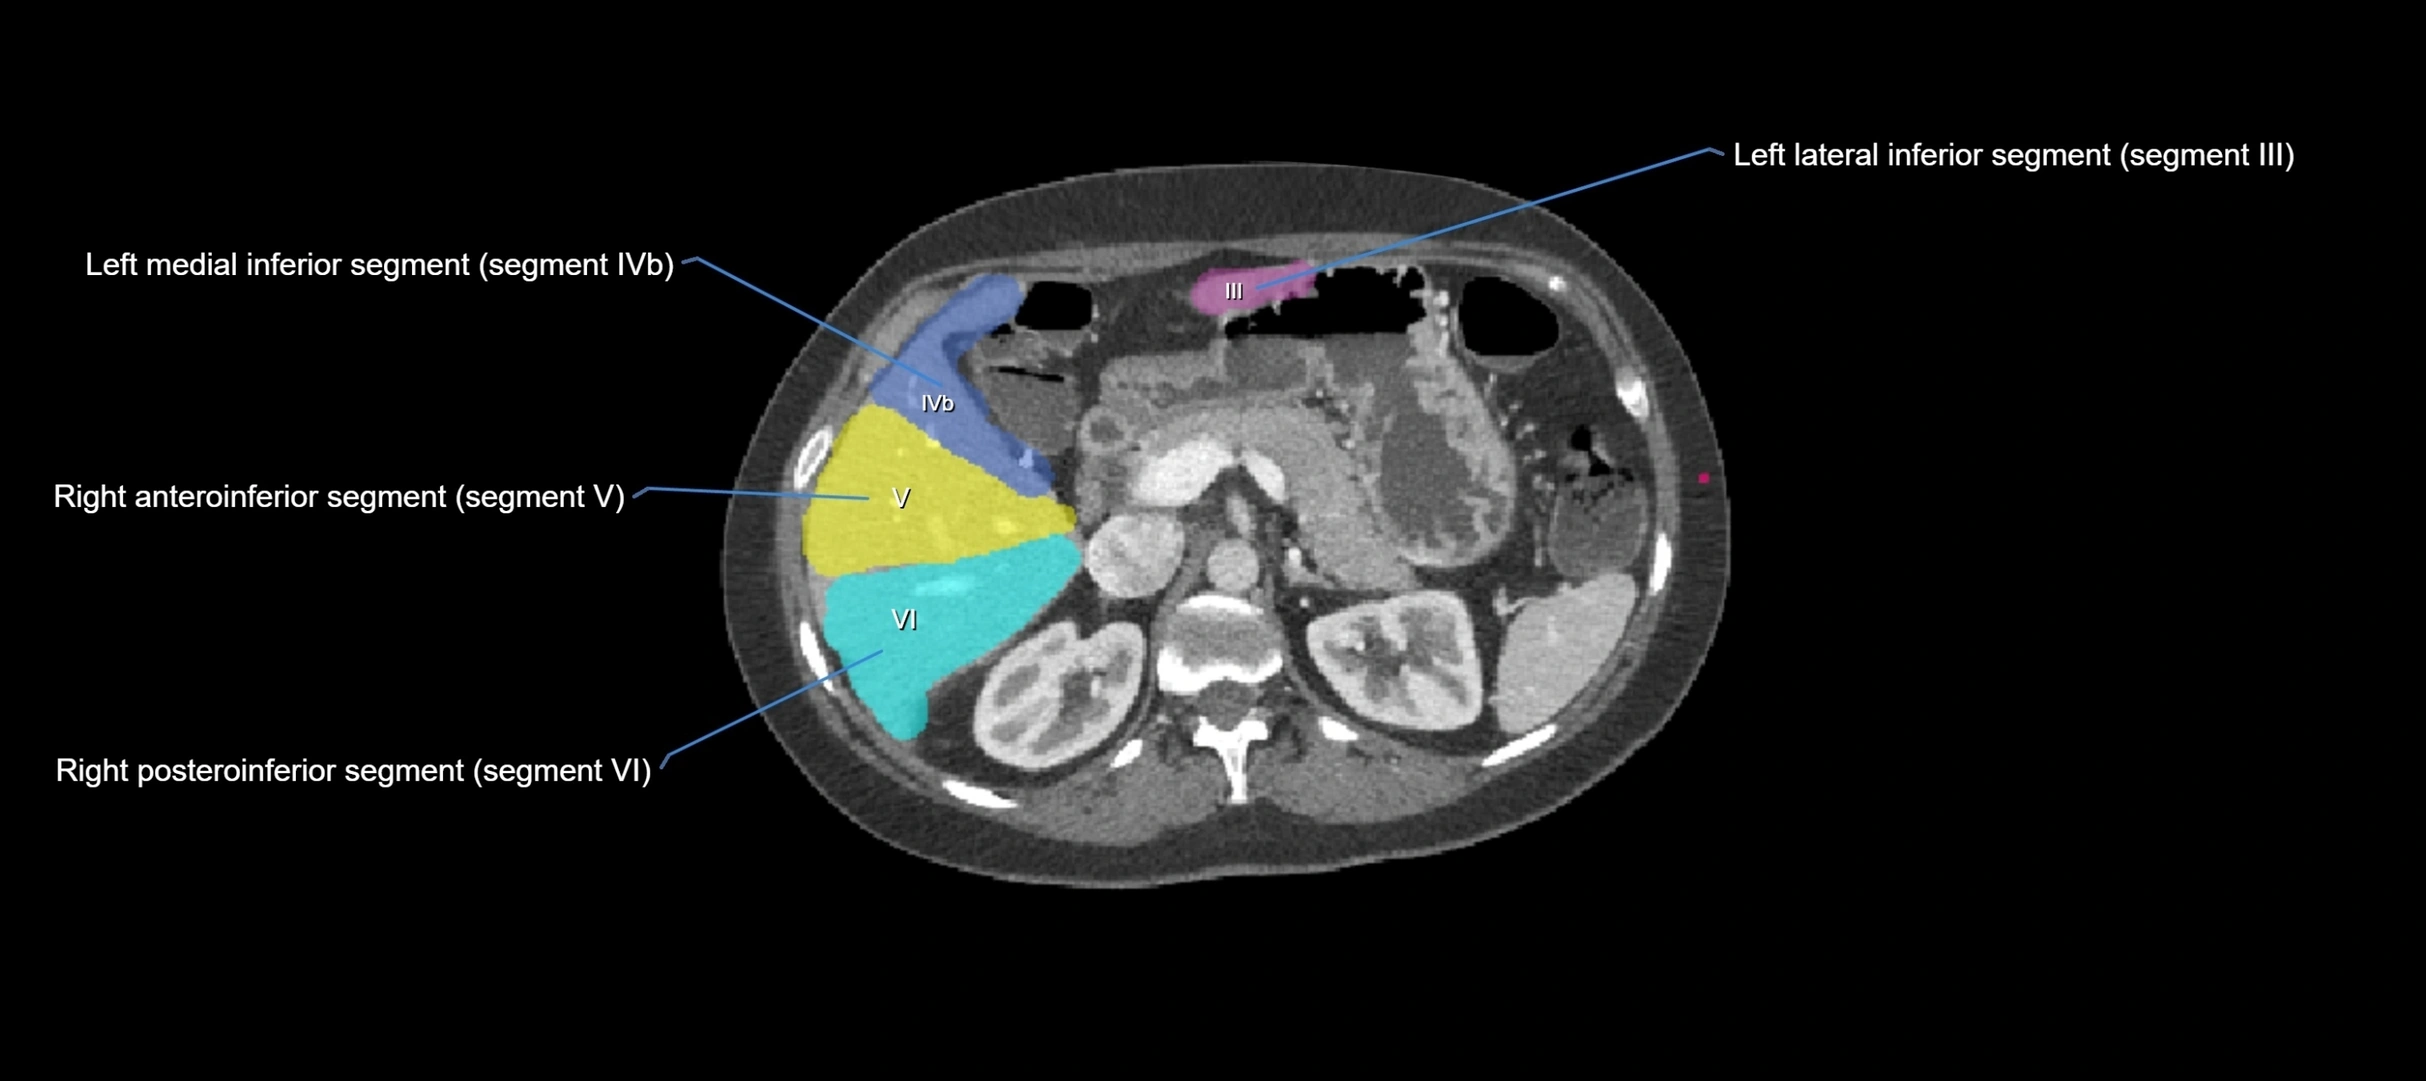

CT Image

image